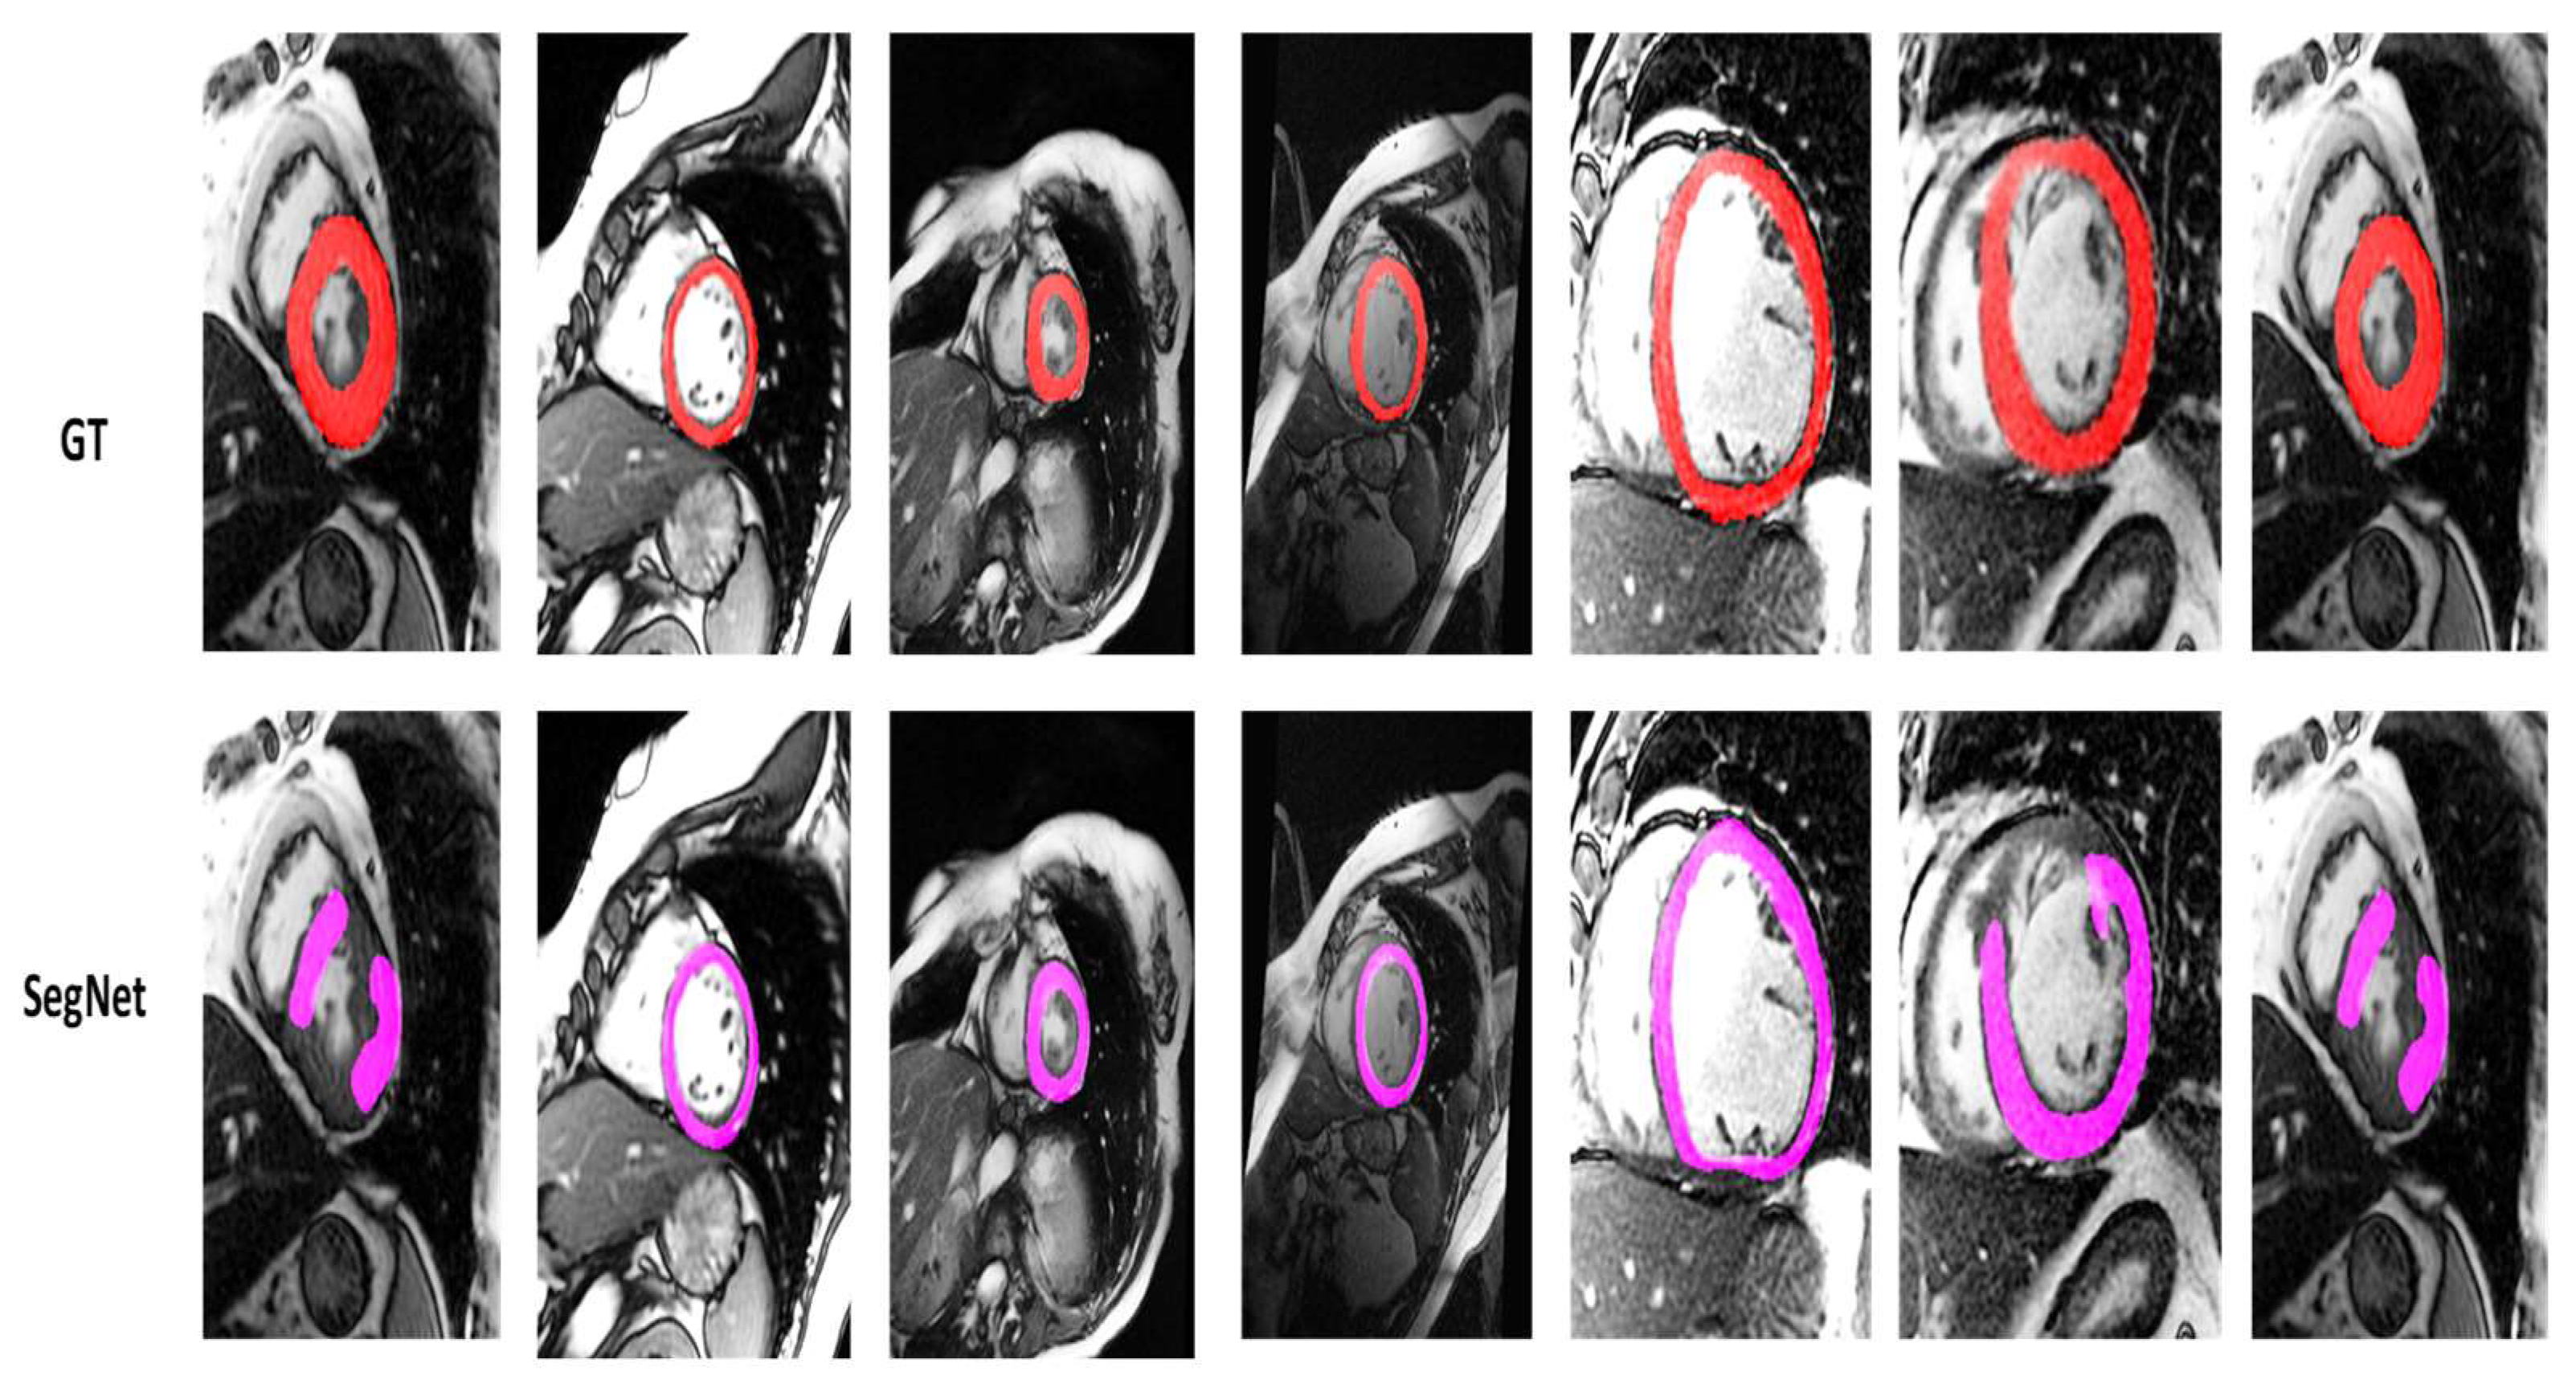

4.2. Visualization Segmentation Results

| SegNetM3 | 81.00 | 69.10 | 8.5227 | 13.6867 | 98.63 | 84.87 | 0.3089 | 2.5484 | 0.1201 |